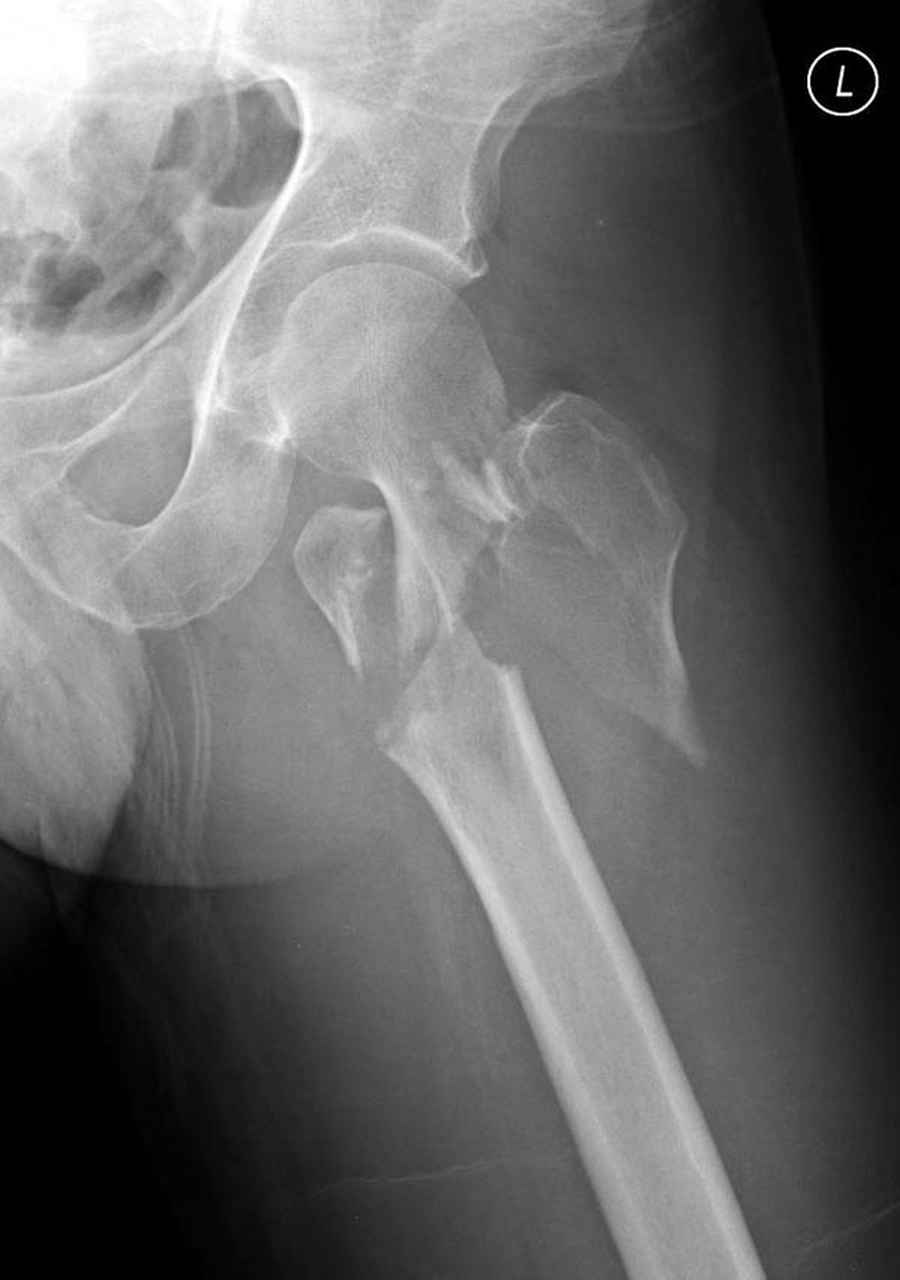

Re: Чрезвертельный перелом бедра

Думаю что перелом всетаки оскольчатый межвертельный, скорее всего использовали бы реконструктивный штифт, но возможно и DHS.

Перелом, на мой взгляд, все-таки чрезподвертельный. Учитывая оскольчатый характер перелома вертельной области, вполне можно рассматривать в качестве альтернативы остеосинтез фиксатором с угловой стабильностью (блокируемая пластина для дистального конца контрлатеральной бедренной кости, производство Синтез или аналог). Конечно, срок ходьбы на костылях будет подольше. Зато картинка посимпатичнее.

По нашему мнению линия перелома проходит вверху через латеральный отдел шейки бедра, вертельная область состоит из нескольких фрагментов. В таких условиях применить DHS или дистальную бедренную пластину LCP представляется нам сомнительным. Закрытый остеосинтез проксимальным гамма-гвоздем или PFNa невозможен т.к. нет ЭОПа.

Возможно открытый остеосинтез гвоздем PFNa?